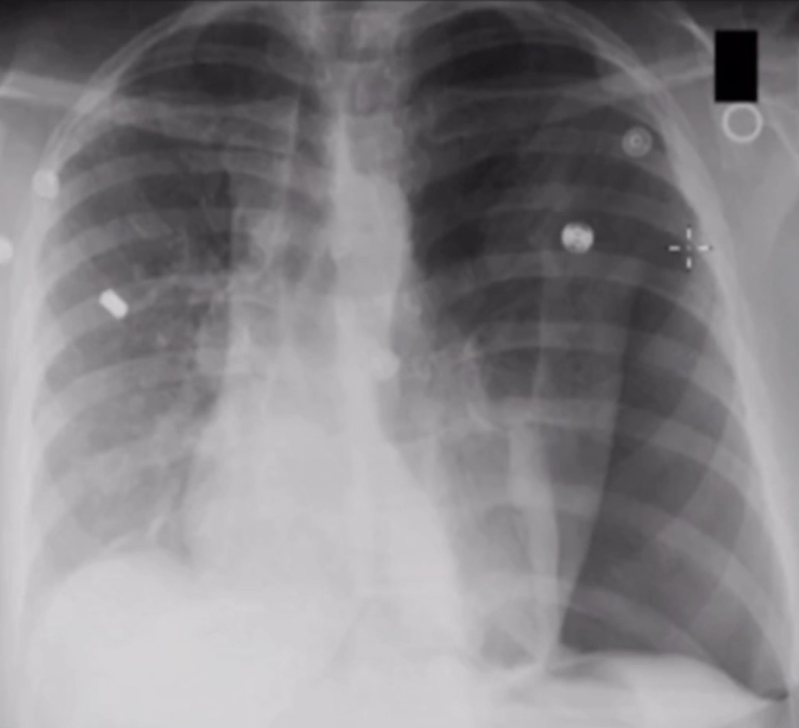

What is the diagnosis based off of this chest x-ray?

Atelectasis

Complete atelectasis of the right side

Left lower lobe pneumonia

42 year old comes in with acute SOB. What is the diagnosis based off of this chest x-ray?

Tension pneumothorax